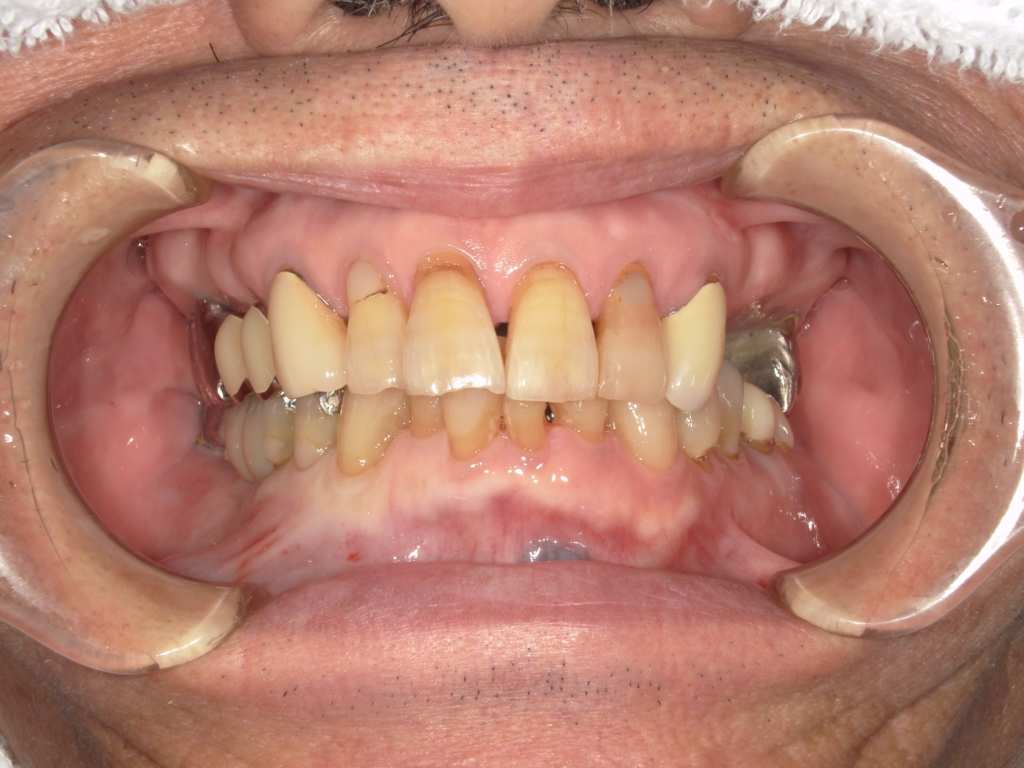

左上の犬歯が虫歯で悪くなってしまい、歯を抜くと同時にインプラントを埋め込んでいます。

3か月ほどでセラミックスの被せものをいれています。(被せものが入るまではインプラントの仮歯)を使ってもらいました。インプラントが入ってからは、左上の奥歯の揺れはなくなりました。